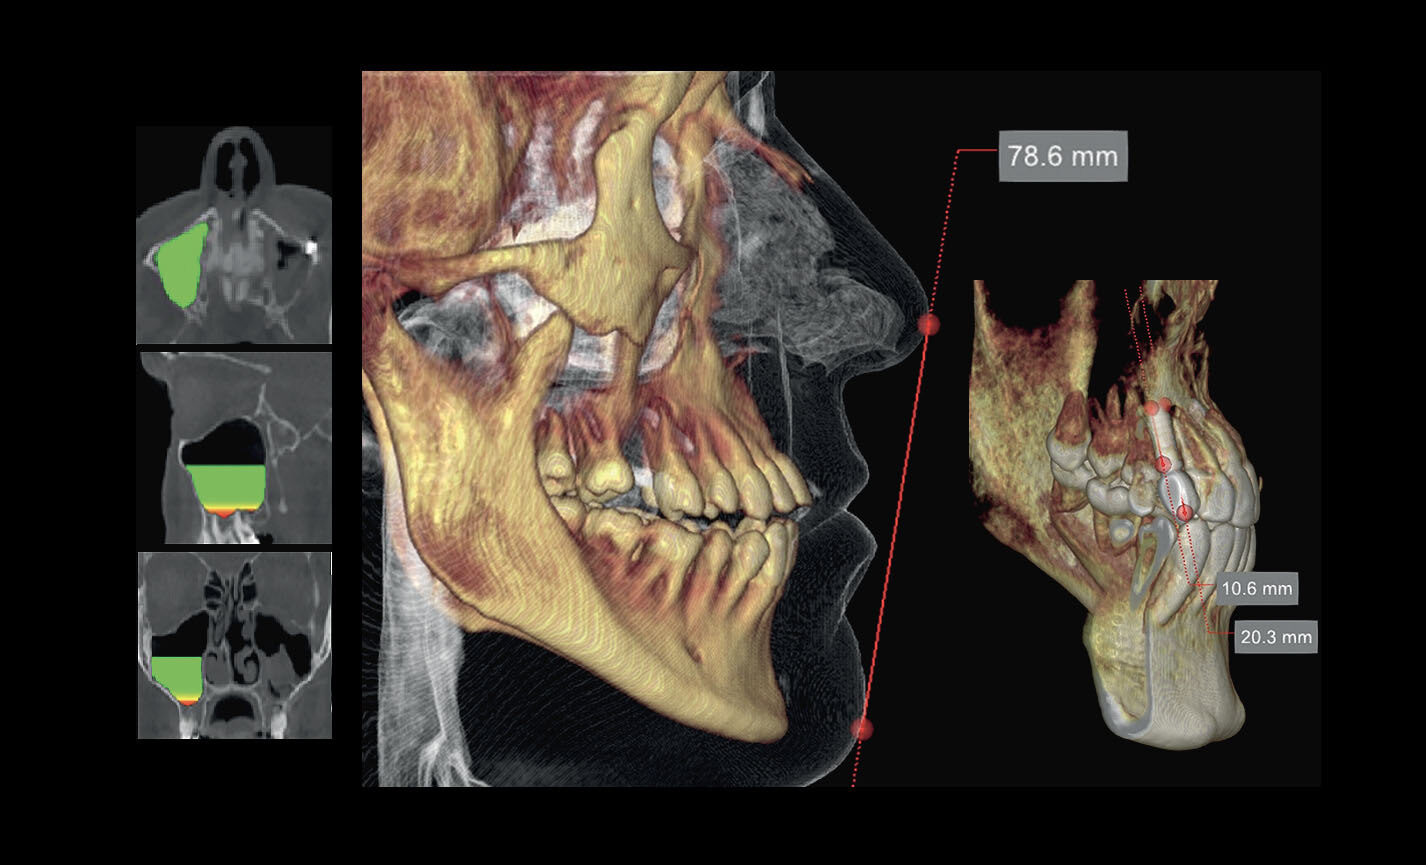

Des FOV de 10 cm de diamètre sont nécessaires pour l’étude des troisièmes molaires incluses car, chez un adulte de taille moyenne, la distance entre les troisièmes molaires de droite et de gauche, en incluant leurs racines respectives, le processus alvéolaire et l’os avoisinant, est d’au moins 9 cm. Les champs de vision réduits sont utiles en cas d’analyse de dents incluses ou surnuméraires, pour limiter la dose à la seule région d’intérêt. En effet, pour une planification correcte du traitement, il est fondamental de déterminer la position réelle (vestibulaire ou palatine), possible uniquement avec une analyse 3D, même à très faible dose avec un protocole QuickScan. Le champ de vision complet 13 x 16 cm permet une évaluation minutieuse des voies aériennes supérieures, souvent utile pour compléter une investigation en vue d’un traitement orthodontique qui tienne compte des problématiques oto-rhino-laryngologiques.

Analyses volumétriques

La fonction du logiciel de calcul du volume de soulèvement du sinus maxillaire permet de déterminer l’intervention à l’avance et d’opérer en toute sécurité. Il est en outre possible de tracer des lignes directement sur le modèle virtuel du patient en évaluant les rapports morphologiques sur le rendu 3D.